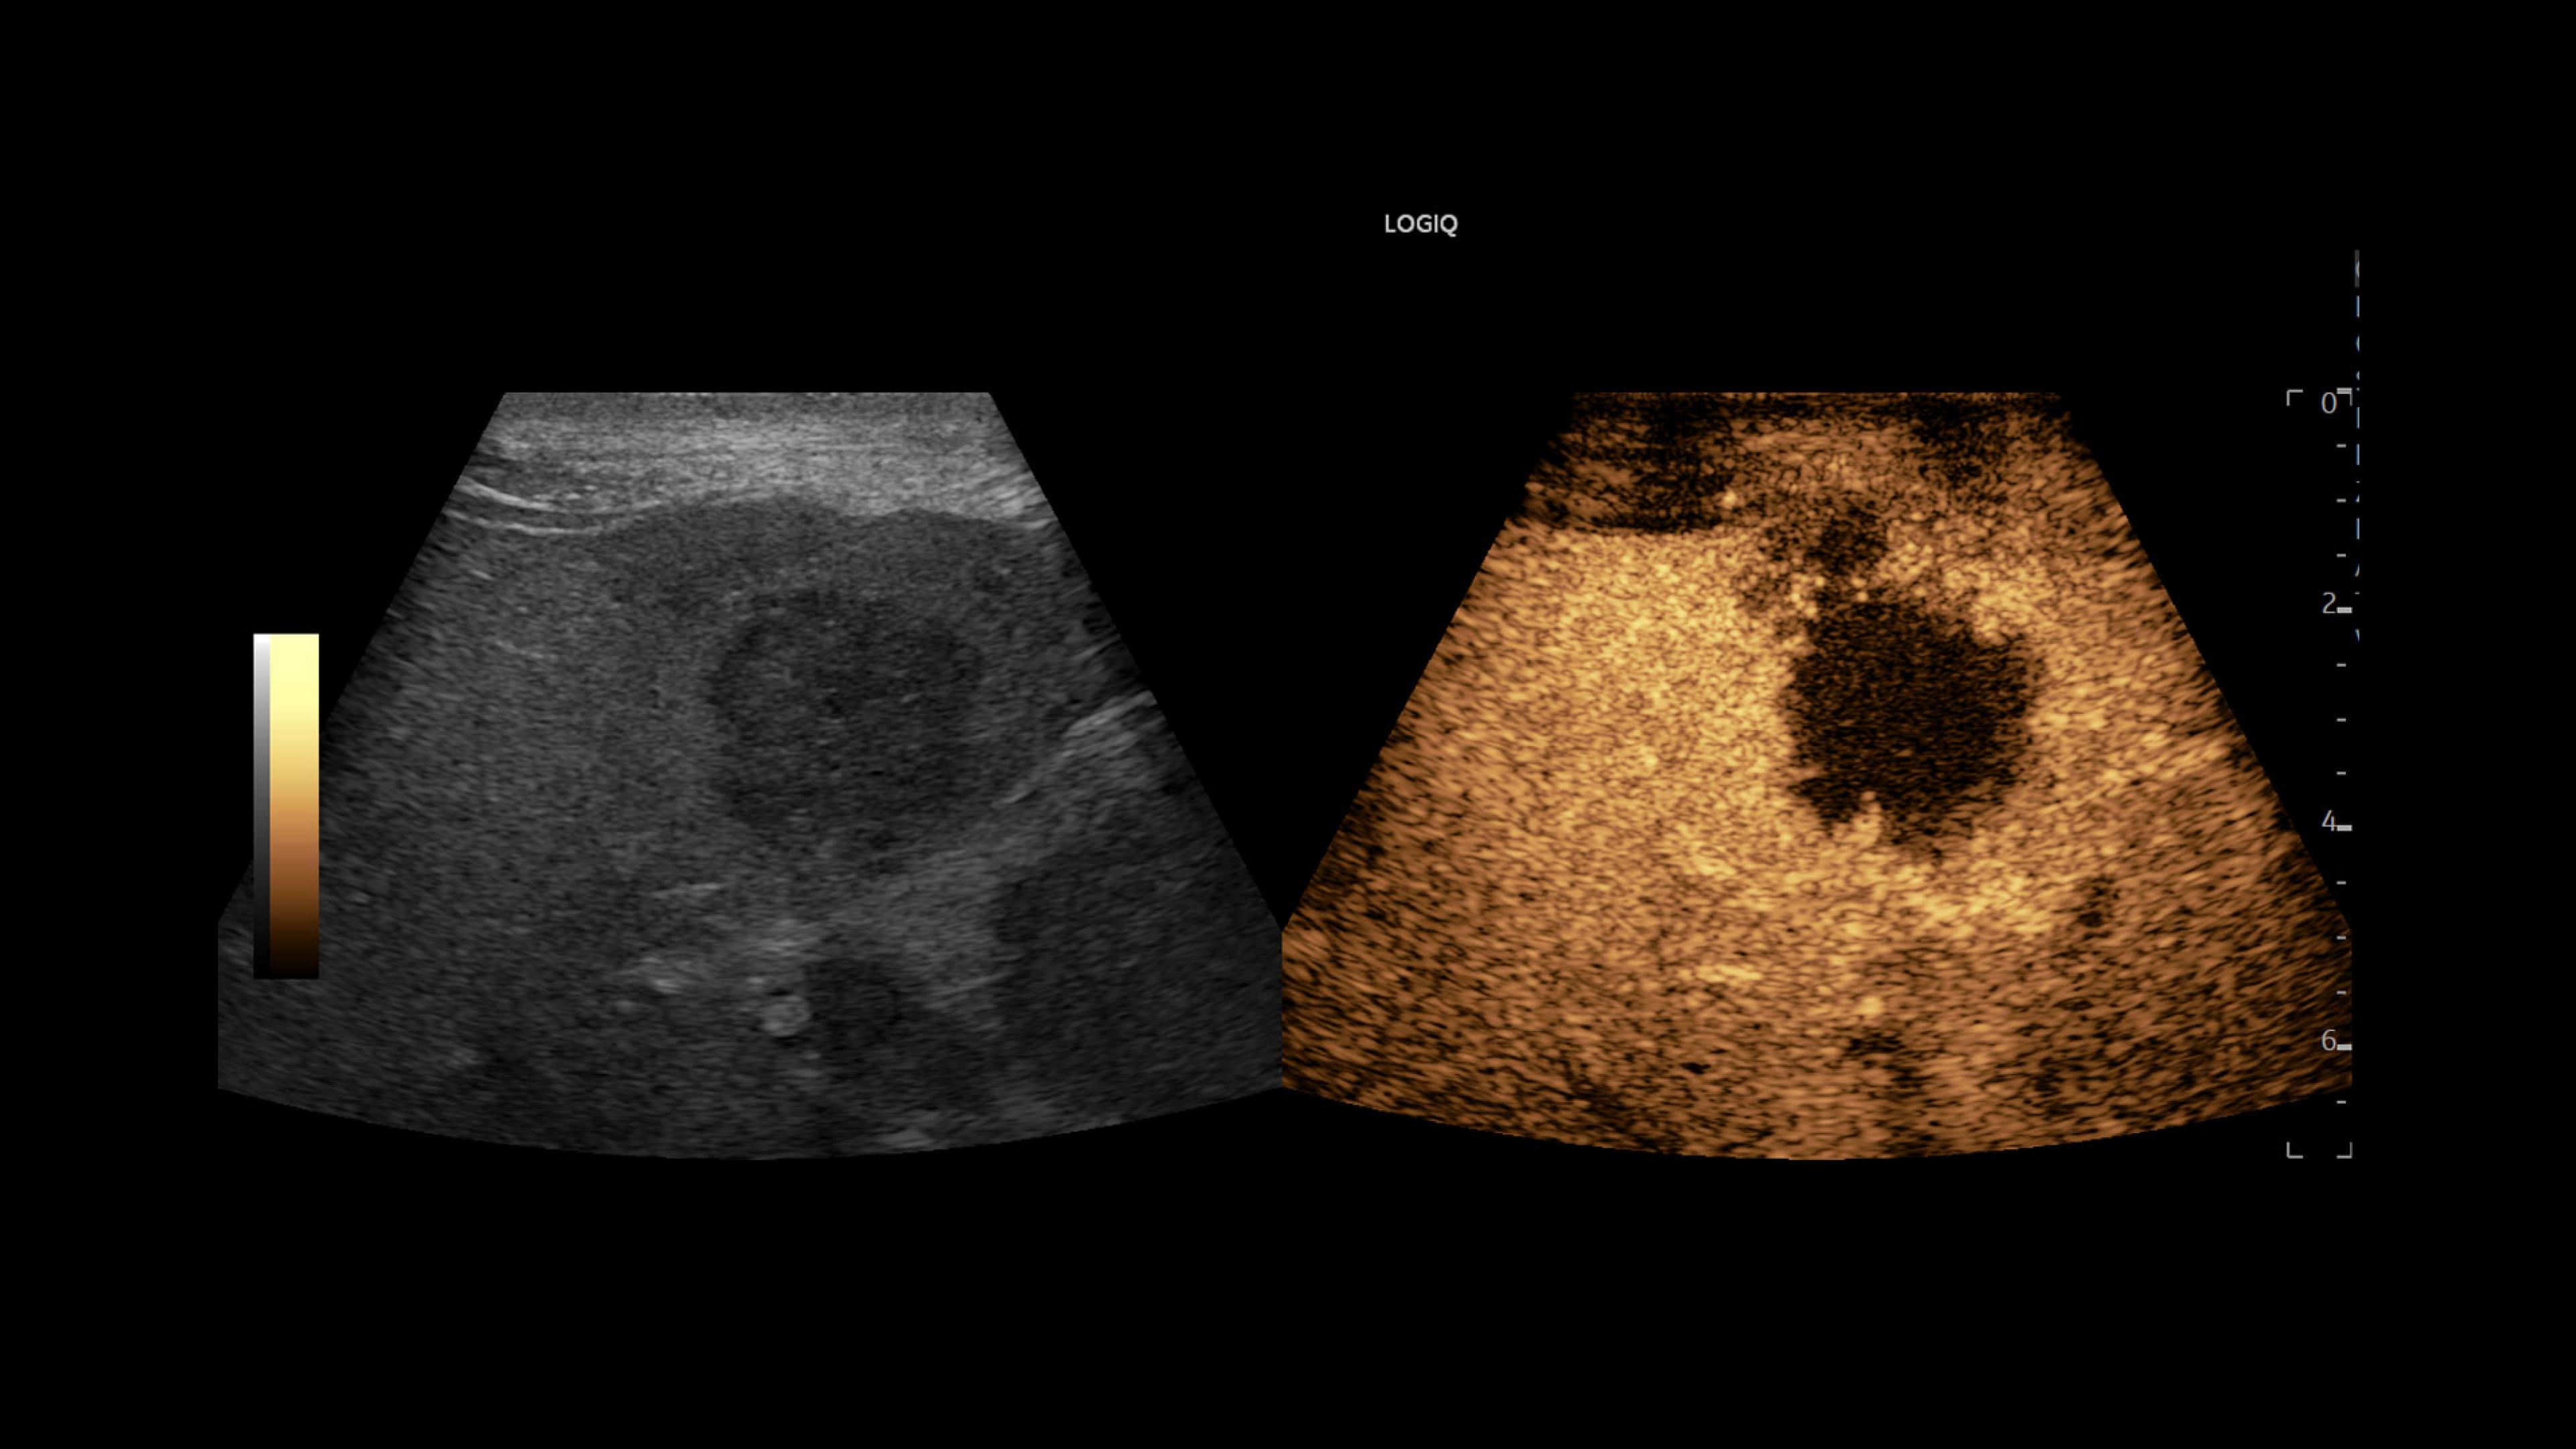

LOGIQ Totus™ Ultrasound

Multi-purpose excellence. Introducing LOGIQ Totus – a head-to-toe, comprehensive ultrasound experience that redefines your expectations.

The LOGIQ Totus™ system is a portable, multi‑purpose, comprehensive solution that combines AI‑powered workflow and decision‑support tools to enhance efficiency and versatility, while its high‑quality imaging supports head‑to‑toe diagnostic confidence.

• Rely on cSound™ Architecture, which delivers exceptional image quality and uniformity

• Leverage a wide range of transducers, including XDclear™, which produces high resolution images covering head-to-toe applications across clinical specialties or care areas

• Address clinically challenging cases with advanced tools such as 2D Shear Wave Elastography, Ultrasound-Guided Attenuation Parameter (UGAP), and Volume Navigation